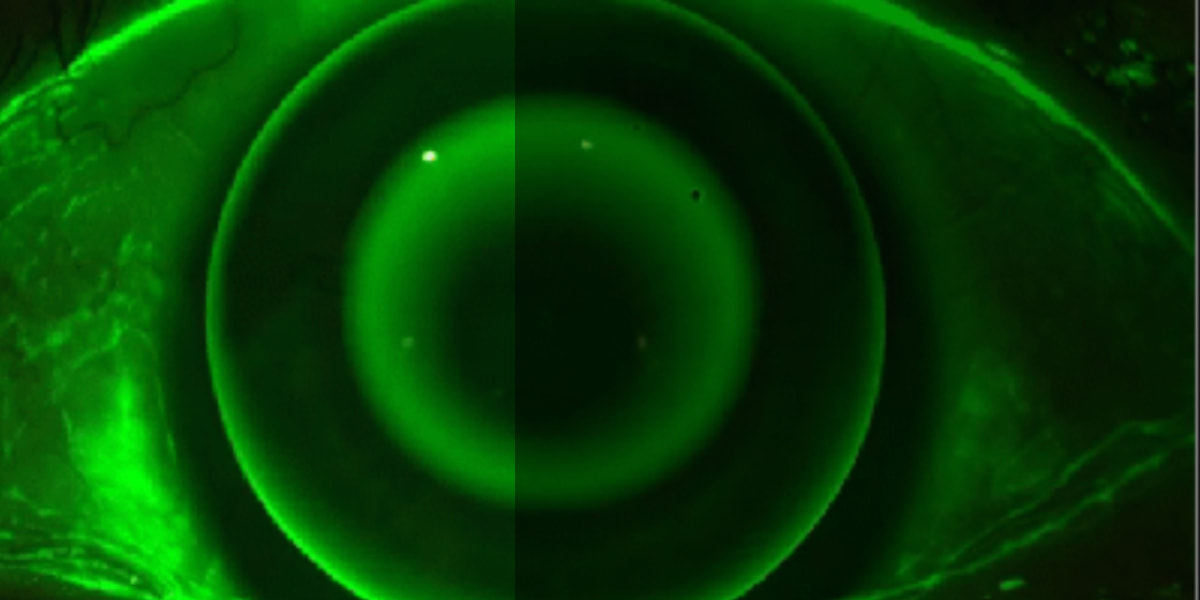

全自动高精度三维眼前节测量,一键完成数据采集与分析。采用微米级三维重构技术,无需人工调节即可获得角膜、前房、晶状体全段精准数据,大幅提升眼科诊断效率,适用于屈光手术规划、白内障术前评估及圆锥角膜筛查等场景。

微米级三维重构,获得角膜、前房、晶状体全段精准数据

圆锥角膜筛查